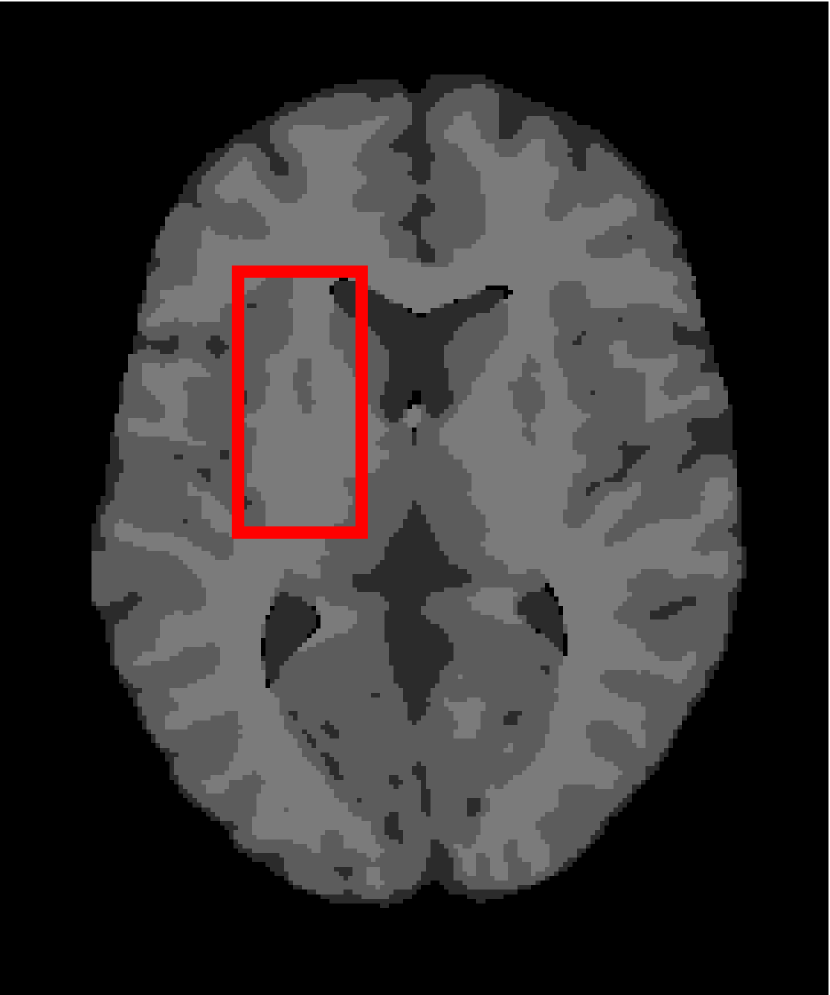

4.4.2 Results on Medical Images

Next, we representatively segment five medical images from BrianWeb. They are represented as five slices in the axial plane with a sequence of 70, 80, 90, 100 and 110, which are generated by T1 modality with slice thickness of 1mm resolution, 9% noise and 20% intensity non-uniformity. Here, we set c=4𝑐4c=4 for all cases. The comparison between WRFCM and its peers are shown in Fig. 9 and Table II. The best values are in bold.

Figure 9: Segmentation results on five medical images. The parameter: ϕ=5.35italic-ϕ5.35\phi=5.35. From top to bottom: noisy images, ground truth, and results of FCM_S1, FCM_S2, FLICM, KWFLICM, FRFCM, WFCM, DSFCM_N, and WRFCM.

TABLE II: Segmentation performance (%) on medical images in BrianWeb

Algorithm Fig. 9 column 1 Fig. 9 column 2 Fig. 9 column 3 Fig. 9 column 4 Fig. 9 column 5

SA SDS MCC SA SDS MCC SA SDS MCC SA SDS MCC SA SDS MCC

FCM_S1 75.756 97.852 96.225 75.026 98.109 96.656 79.792 98.452 97.334 81.887 98.614 97.680 81.869 94.254 90.947

FCM_S2 75.769 98.119 96.664 74.970 98.176 96.765 79.886 98.458 97.338 82.073 98.625 97.695 81.788 98.223 97.195

FLICM 74.998 98.070 96.568 74.185 98.122 96.660 79.099 98.515 97.432 81.447 98.627 97.691 81.668 98.273 97.260

KWFLICM 74.840 98.259 96.878 73.839 97.860 96.190 79.560 98.453 97.316 81.887 98.482 97.443 81.370 98.297 97.286

FRFCM 75.853 97.620 95.775 75.514 97.660 95.830 80.283 98.278 97.013 81.852 98.319 97.171 81.666 98.079 96.945

WFCM 75.507 97.124 94.957 74.471 97.213 95.045 79.316 97.845 96.283 81.358 97.546 95.211 81.452 95.247 92.501

DSFCM_N 76.400 92.325 86.262 75.288 91.574 85.095 79.861 97.678 95.996 81.831 93.304 88.829 81.750 94.302 91.024

WRFCM 82.317 98.966 98.147 82.141 98.298 96.970 83.914 98.963 98.202 83.533 99.170 98.603 84.615 98.429 97.511

By a view of the marked red square in Fig. 9, we find that FCM_S1, FCM_S2, FLICM, KWFLICM and DSFCM_N are vulnerable to noise and intensity non-uniformity. They give rise to the change of topological shapes to some extent. Unlike them, FRFCM and WFCM achieve sufficient noise removal. However, they produce overly smooth contours. Compared with its seven peers, WRFCM can not only suppress noise adequately but also acquire accurate contours. Moreover, it yields the visual result closer to ground truth than its peers. As Table II shows, WRFCM obtains optimal SA, SDS and MCC results for all five medical images. As a conclusion, it outperforms its peers visually and quantitatively.